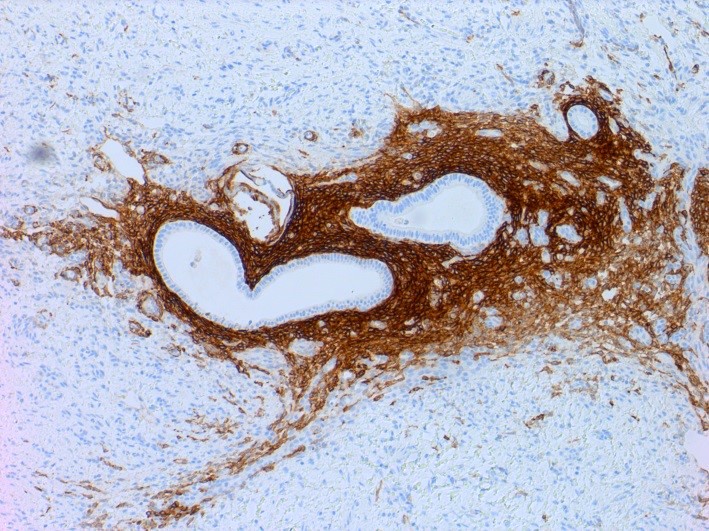

Microscopic (histologic) description

- At least 2 of the following 3 features

- Endometrial type glands

- Müllerian type epithelium (can be atrophic to cycling endometrium)

- Endometrial type stroma

- Often contains fine capillary network

- May undergo smooth muscle metaplasia, fibrosis (longstanding), decidual change

Microscopic (histologic) images

Positive stains

- CD10 is positive in endometrial stroma

- ER, PR and PAX2 are often positive in endometrial glands and stroma (Am J Surg Pathol 2013;37:1342)